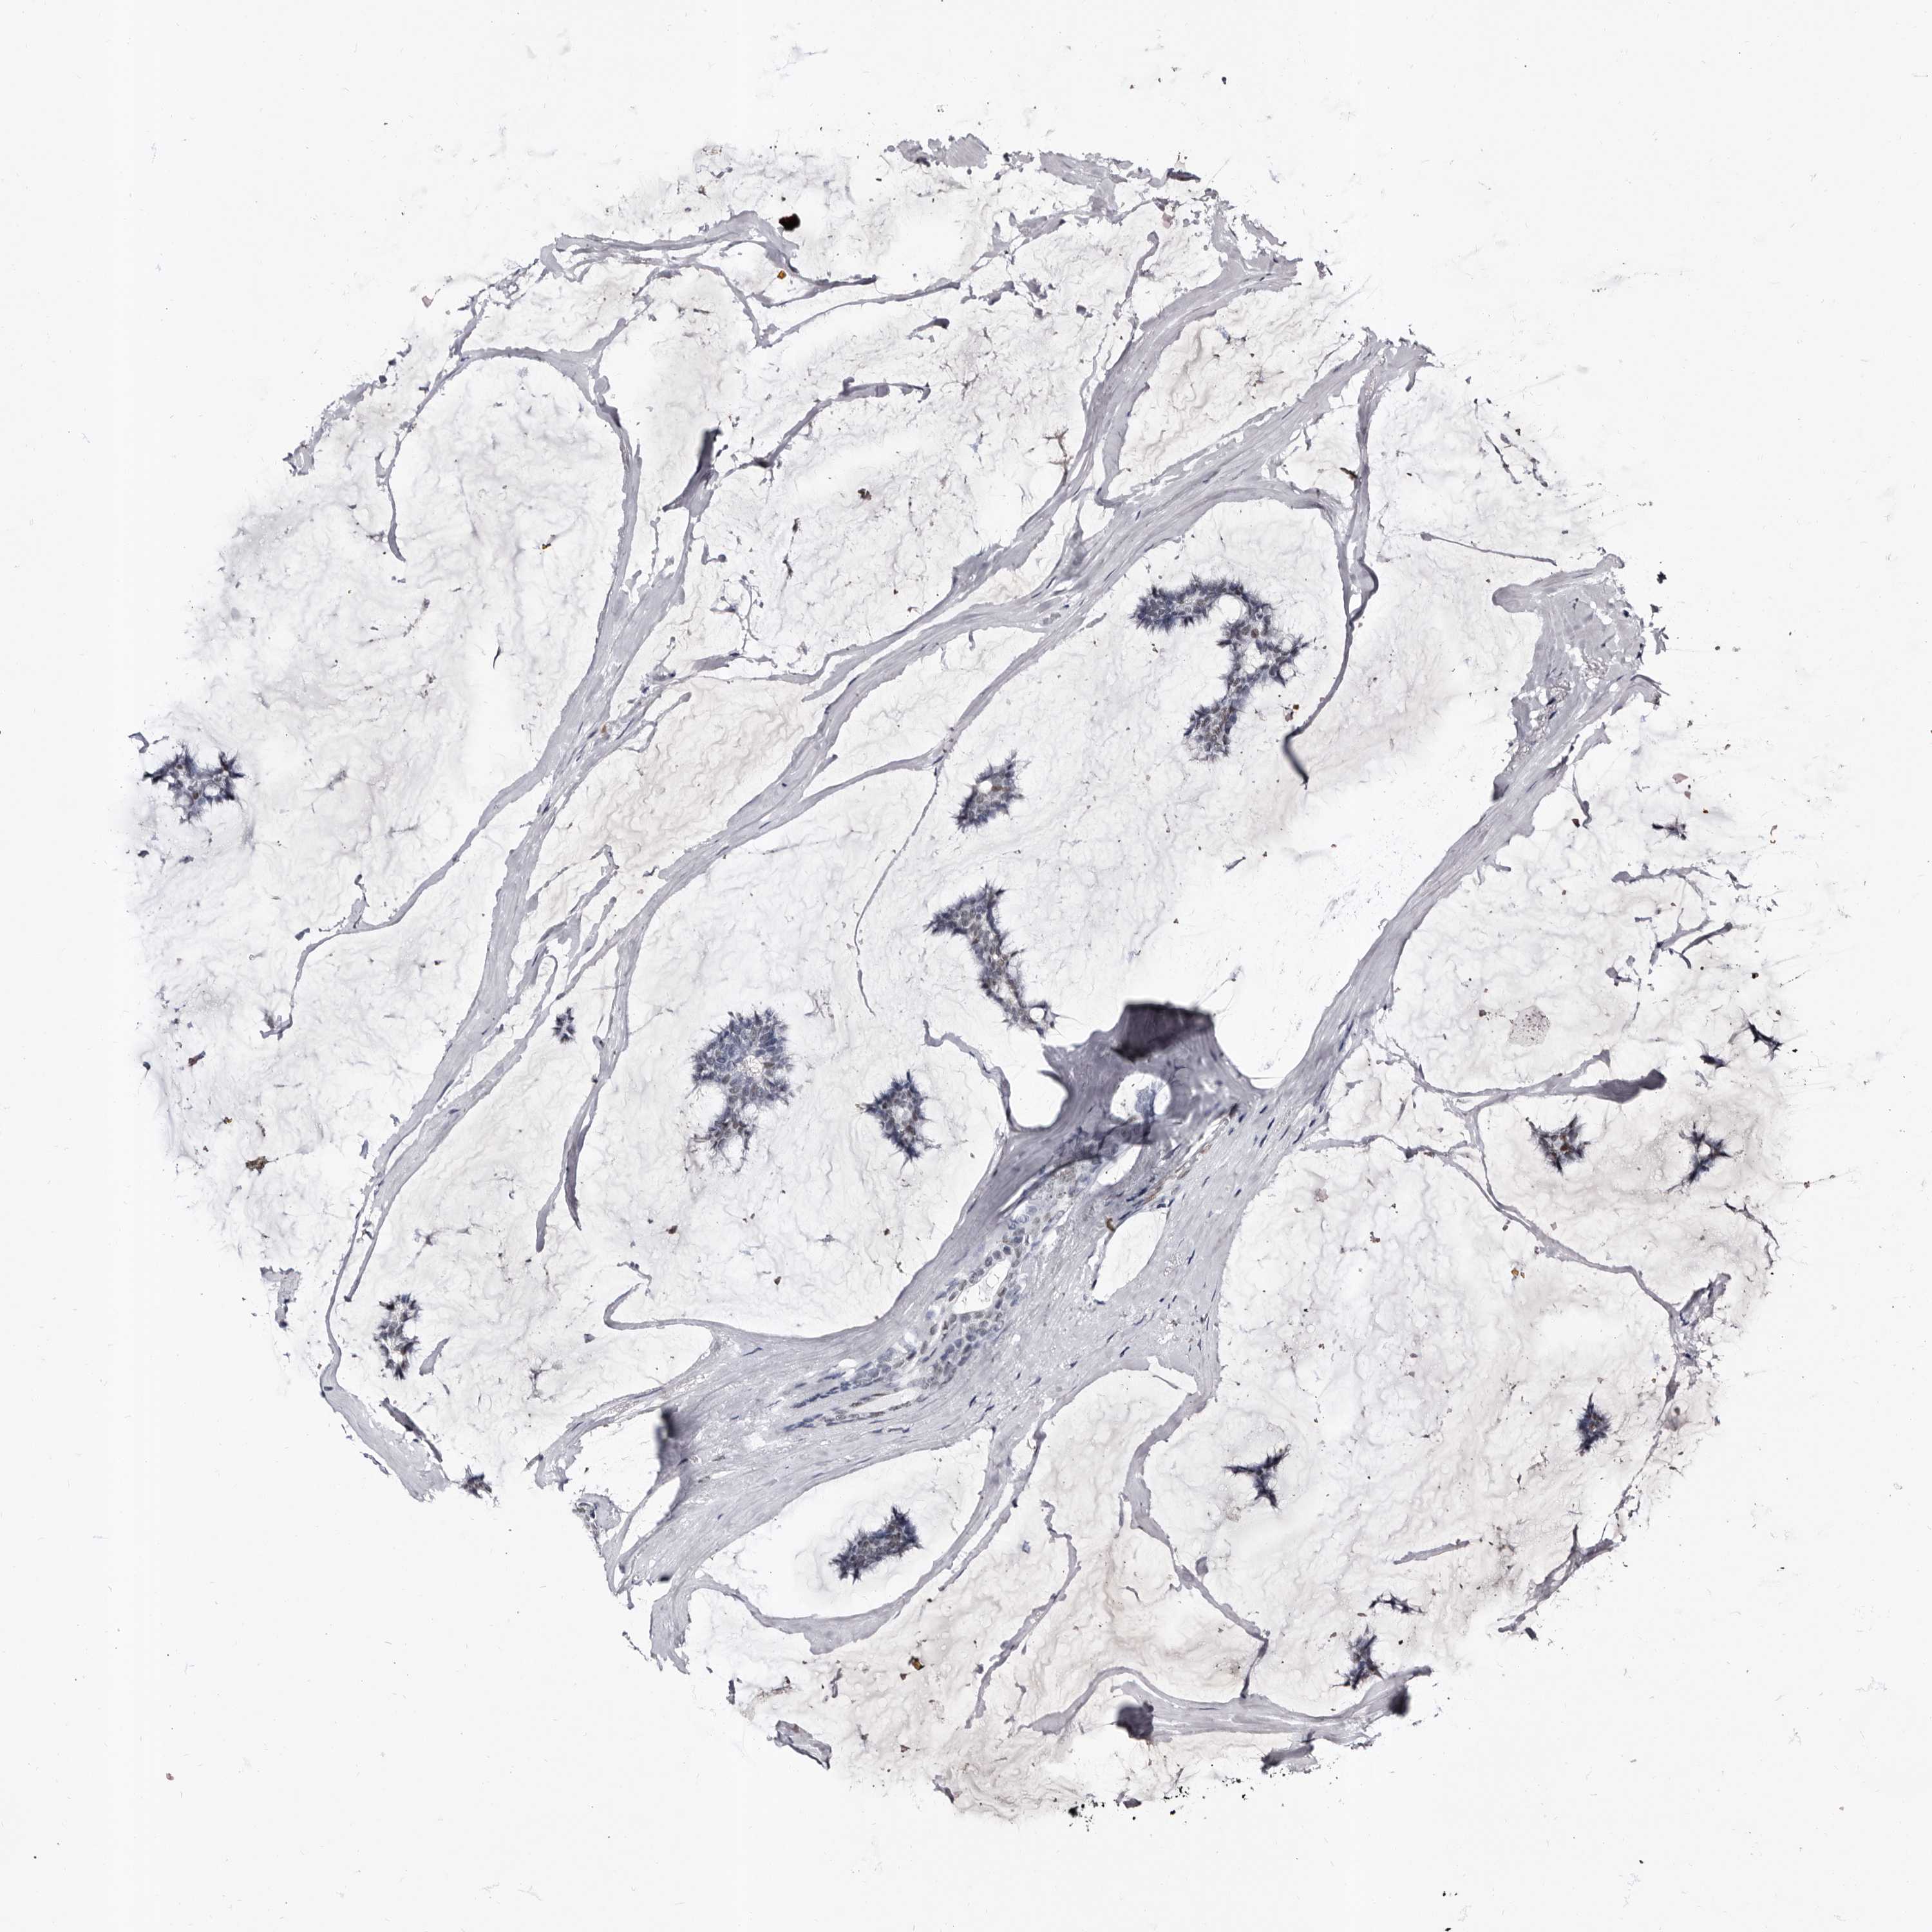

CANCER BREAST CANCER Show tissue menu

BRCA TCGA BRCA VALIDATION PROTEIN EXPRESSION

ANTIBODIES

AND

VALIDATION